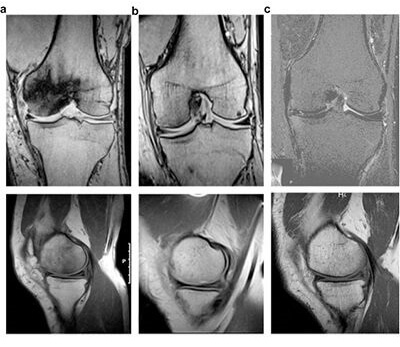

Femoral condylar necrosis: treatment with hyperbaric oxygen therapy

https://doi.org/10.1016/j.artd.2018.02.010